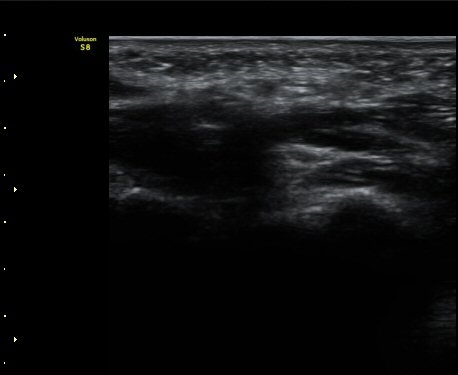

Äá¾Ë»À(pisiform) ºÎÀ§ ô°ñ½Å°æ Ⱦ´Ü¸é°Ë»ç¿¡¼­ Á¤Á߽Űæ°ú ô°ñ½Å°æÀÌ Á¤»óÀûÀÎ ¸ð½ÀÀ¸·Î

°üÂûµÈ´Ù(»çÁø 2).